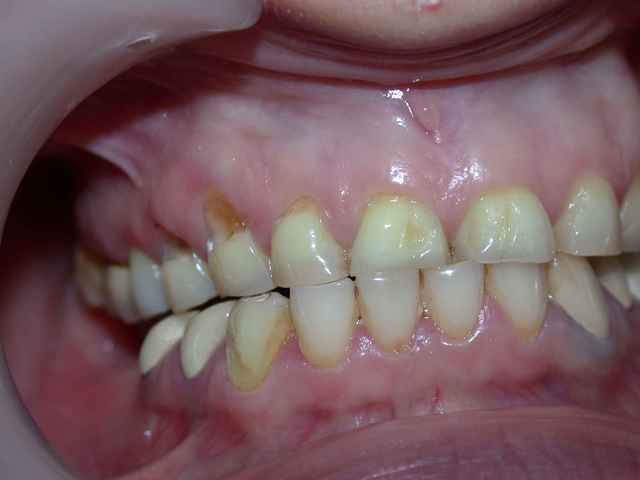

photos et pano du cas initial .

murielle a posté sur un cas de bruxisme en demandant quelle solution envisagée

alors je me lance et propose un cas similaire réalisé en plusieurs étapes ...